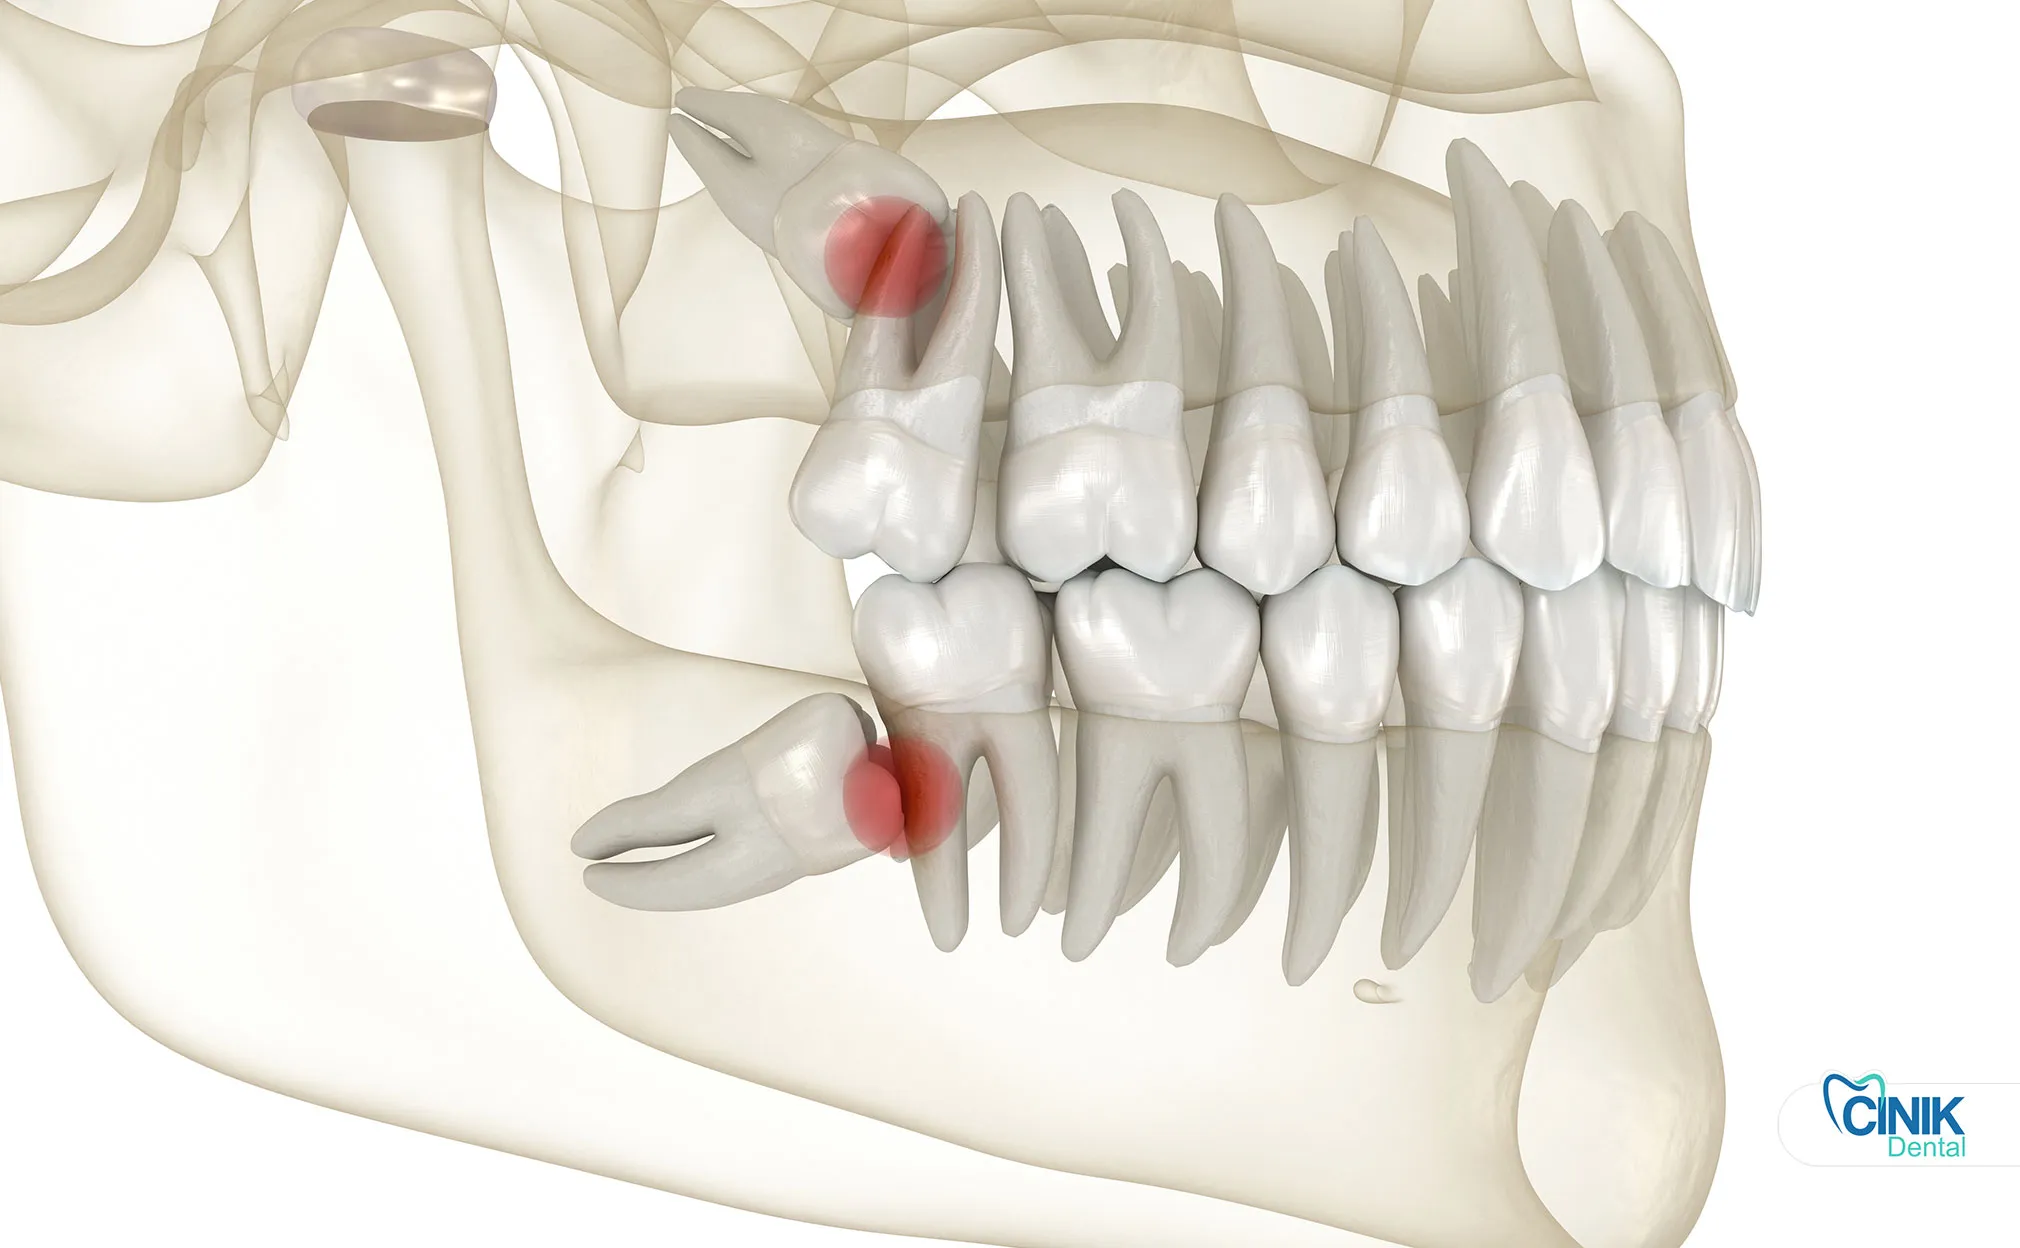

Contemporary epidemiological studies reveal that impacted wisdom teeth affect approximately 24% to 35% of the global population (Gbotolorun et al., 2017). Impaction occurs when a tooth lacks sufficient space to erupt fully into its functional position. This anatomical constraint creates a cascade of clinical challenges that modern dentistry must address through evidence-based third molar extraction protocols.

Anatomical positioning varies significantly between maxillary (upper) and mandibular (lower) third molars. Maxillary wisdom teeth typically present simpler surgical profiles due to less dense surrounding bone and favorable root morphology. Conversely, mandibular third molars pose greater technical challenges because of their proximity to the inferior alveolar nerve and the mandible's dense cortical bone (Bui et al., 2019).

The relationship between wisdom teeth and critical anatomical structures demands precise preoperative assessment. The inferior alveolar nerve courses through the mandible, supplying sensation to the lower lip and chin. Approximately 12% to 20% of mandibular third molars demonstrate radiographic superimposition with this nerve canal, elevating paresthesia risks during extraction (Guerrero et al., 2020). Similarly, maxillary third molars may project roots into the maxillary sinus, creating potential oroantral communication risks.